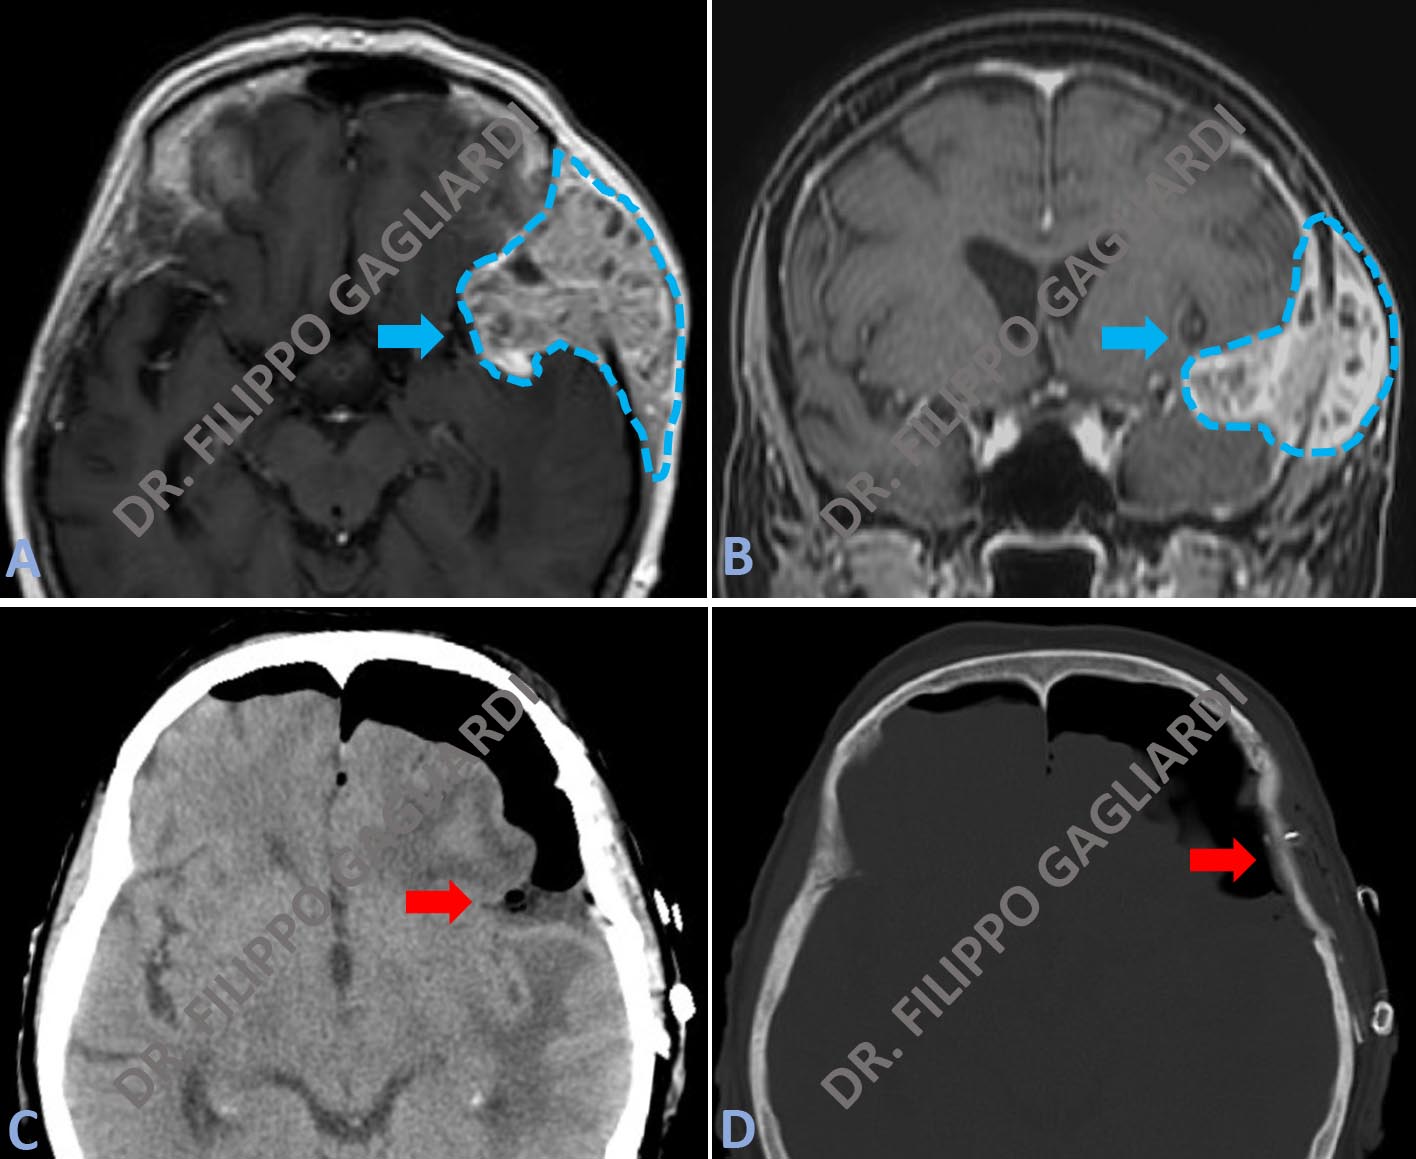

Caso di linfoma primitivo cerebrale in una Paziente sottoposta a biopsia stereotassica. La biopsia stereotassica è una procedura ad altissima precisione. Attraverso un sottile ago, consente di prelevare tessuto cerebrale per eseguire una diagnosi istologica nel caso di patologie intracraniche. Il sistema stereotassico si avvale di un casco che viene posizionato al paziente prima della procedura bioptica e che rappresenta un sistema di massima affidabilità per la localizzazione di target intracranici. Questa metodica minimizza i rischi di complicanze e massimizzare le possibilità diagnostiche in caso di lesioni profonde in aree critiche. La figura A mostra l’esame spettroscopico preoperatorio. Si tratta di un esame non invasivo. Viene eseguito con l'apparecchiatura di RM che, campionando il tessuto patologico, ne analizza la composizione chimica. L’esame era suggestivo, per l’elevata concentrazione di alcuni elementi chimici, per linfoma primitivo cerebrale. La figura B mostra lo studio di RM standard con mezzo di contrasto, che definisce la morfologia della lesione a livello del tronco dell’encefalo. Infine la figura C illustra invece il controllo della TC post-operatoria, dove si può apprezzare la precisione del prelievo bioptico (area nera).

Caso di astrocitoma pilocitico, tumore primitivo del cervelletto, in una bambina di 10 anni con vomito e cefalea. Le figure A e B mostrano rispettivamente la sequenza assiale e sagittale (laterale) della RM pre-operatoria. La voluminosa lesione prende contrasto in modo disomogeneo. Condiziona la compressione del cervelletto e del tronco cerebrale (struttura anatomica ad altissimo contenuto funzionale, che regola l’attività cardiaca e respiratoria). La giovane Paziente è stata sottoposta ad intervento di craniectomia sub-occipitale ed exeresi radicale della lesione. Le figure C e D illustrano il controllo post-operatorio, dove non si apprezza più il tessuto patologico.